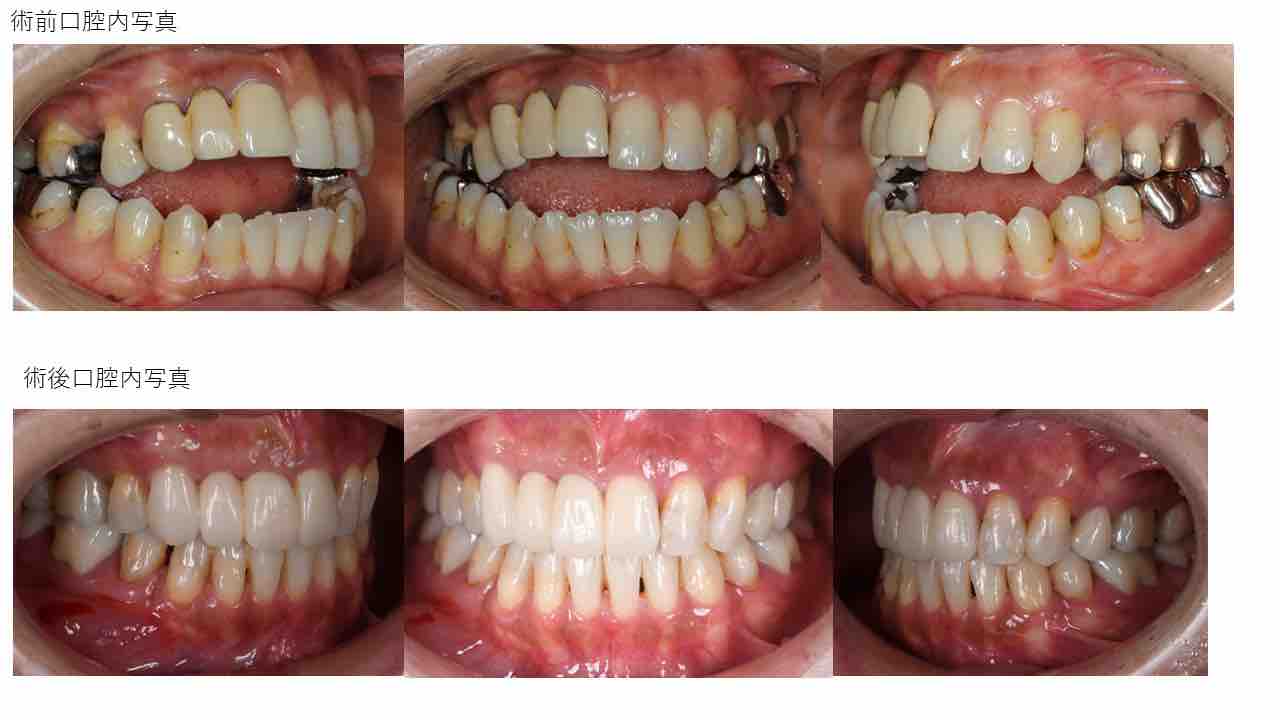

Èþ¤·¤¤¸ý¸µ¤Ë¡¡Ã°Ìî»õ²Ê¶ºÀµ¼£ÎŪ

Èþ¤·¤¤¸ý¸µ¤Ë¡¡Ã°Ìî»õ²Ê¶ºÀµ¼£ÎÅ©

Èþ¤·¤¤¸ý¸µ¤Ë¡¡Ã°Ìî»õ²Ê¶ºÀµ¼£ÎŨ

Èþ¤·¤¤¸ý¸µ¤Î¡¡Ã°Ìî»õ²Ê¶ºÀµ¼£Îŧ

Èþ¤·¤¤¸ý¸µ¤Ë¡¡Ã°Ìî»õ²Ê¶ºÀµ¼£ÎŦ

Èþ¤·¤¤¸ý¸µ¤Ë¡¡Ã°Ìî»õ²Ê¶ºÀµ¼£ÎÅ¥

Èþ¤·¤¤¸ý¸µ¤Ë¡¡Ã°Ìî»õ²Ê¶ºÀµ¼£ÎŤ

Èþ¤·¤¤¸ý¸µ¤Ë¡¡Ã°Ìî»õ²Ê¶ºÀµ¼£ÎÅ£

Èþ¤·¤¤¸ý¸µ¤Ë¡¡Ã°Ìî»õ²Ê¶ºÀµ¼£ÎÅ¢

Èþ¤·¤¤¸ý¸µ¤Ë¡¡Ã°Ìî»õ²Ê¶ºÀµ¼£ÎÅ¡